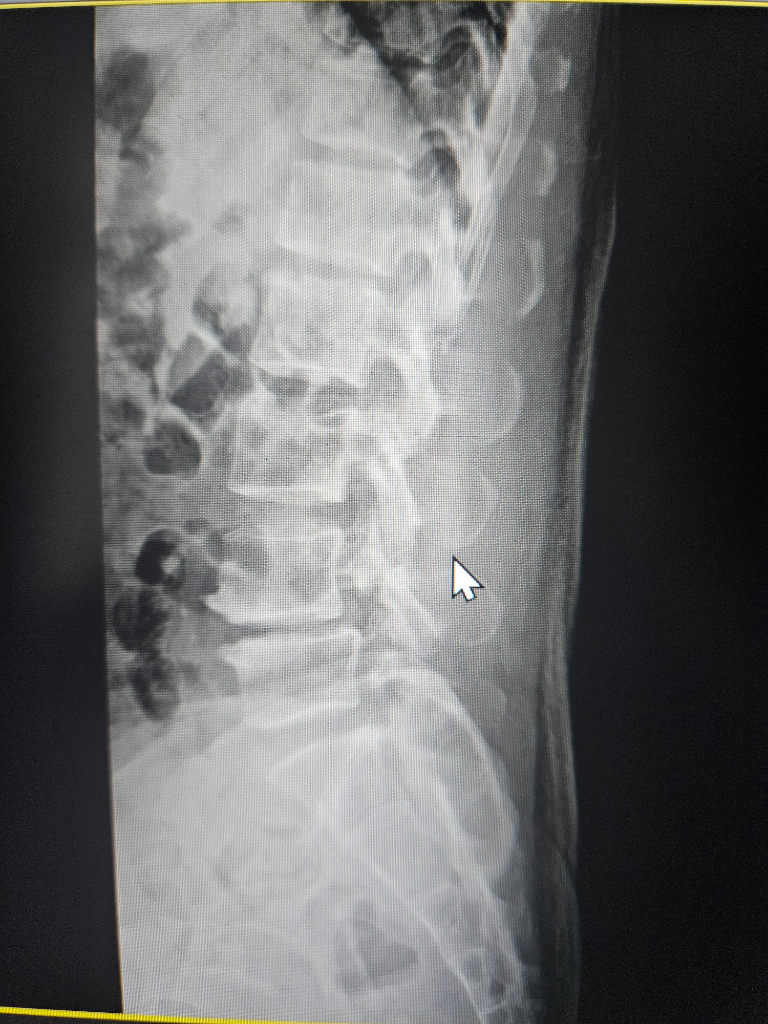

수술해야될 정돈지 사진보시고 확인좀 해주세요

척추분리증과 전방전위증등으로 통증이 너무심한데

허리부터 다리까지 통증이 있고 종아리까지 전기가 찌릿한 증상 누워있을때는 그나마 참을만 한데 그외 다른자세를 하면 통증이 심해집니다

걷는것도 10분이상하면 허리 부터 허벅지 까지 통증이 심하게 생깁니다

척추분리증은 30년 정도 되었고 다른건 10년이 넘은거 같습니다

사진과함께 증상을 종합해봤을때 수술이 필요한지 아니면 보존치료가 더 나은지 궁금 합니다

보내주신 사진만으로는 정확한 진단을 내리기 어렵습니다. 정확한 진단을 위해서는 전문의의 진찰과 검사가 필요합니다. 하지만 사진과 증상을 종합해보면 수술을 고려해볼 수 있는 수준으로 보입니다.

척추분리증과 전방전위증은 척추뼈가 정상적인 위치에서 벗어나 발생하는 질환입니다. 이 질환은 허리와 다리에 통증, 저림, 감각 이상 등의 증상을 유발할 수 있습니다.

수술 방법은 여러 가지가 있으며, 환자의 상태에 따라 적절한 방법을 선택합니다. 일반적으로 척추뼈를 고정하는 척추유합술이 시행됩니다.